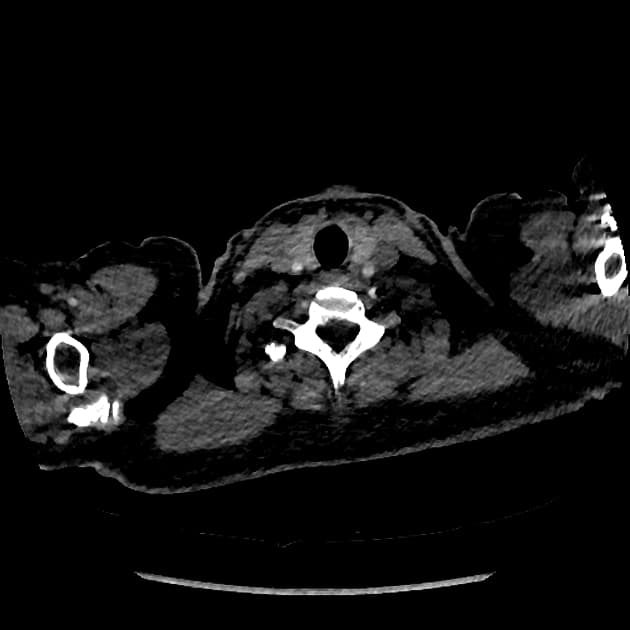

- Không thấy hình ảnh (no evidence of) vỡ thất, nhưng hình ảnh động (cine images) cho thấy thành trước giữa thất trái bị rối loạn vận động (dyskinetic), phồng ra ngoài trong thì tâm thu.

- Trên hình STIR, đoạn cơ tim tổn thương tăng tín hiệu (hyperintense), phù hợp với phù (edema).

- Không thấy huyết khối (thrombus) trên hình gadolinium sớm, và không thấy tăng quang cơ tim (myocardial hyperenhancement) trên hình gadolinium muộn.

- Có tràn dịch màng ngoài tim lượng nhỏ (small pericardial effusion).

- Vị trí tổn thương là bất thường, vì thường thì các đoạn đỉnh (apical segments) bị ảnh hưởng trong bệnh lý này. Tuy nhiên, ba kiểu hình ảnh khác biệt đã được ghi nhận: hai thất (biventricular), giữa thất (mid-ventricular – như trường hợp này), và đoạn đáy (basal).

- Trên cộng hưởng từ (MRI), các phát hiện điển hình gồm phù cơ tim (myocardial edema) và không có thiếu máu cục bộ (ischemia) hay xơ hóa (fibrosis), điều này được chứng minh bằng việc không tăng quang ở thì muộn sau tiêm gadolinium (lack of enhancement at late gadolinium imaging).